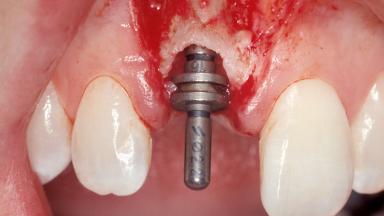

Immediate Placement of an Implant in a Maxillary Right Central Incisor Site

A 30-year-old female patient was referred to the office for the treatment of tooth 11. Her chief concern at the initial visit was to inquire, “Why is my tooth pink?” Upon clinical examination, it was determined that tooth 11 had a previous history of trauma and that the clinical crown had become noticeably pink in color as a result of internal resorption. This diagnosis was confirmed radiographically, indicating a large radiolucency involving the central and distal portions of the clinical crown. It was determined that restoration of this tooth was not possible, and that extraction was indicated. The presence of a mid-line diastema, which the patient wanted to reproduce, directed the treatment plan for tooth replacement utilizing a dental implant.

Type of Implants One-Piece|Reduced-Diameter

Attachment One-Piece|Reduced-Diameter

Placement Protocol Immediate implant placement

Tooth Site Maxillary incisor or canine

Socket Morphology Single-root socket

Socket Integrity Sufficient, with intact bone walls

Bone Volume Sufficient, with intact walls